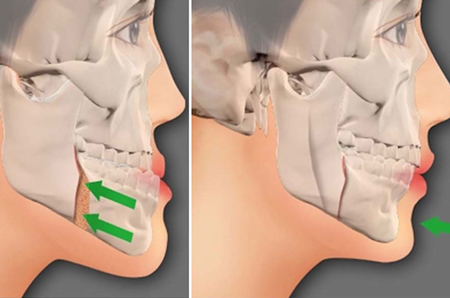

جراحی فک پائین

افرادی که دارای فک پائین بیش از حد بیرون زده یا بی اندازه عقب رفته هستتند می توانند تا حد زیادی با انجام جراحی فک از ظاهر و عملکرد مطلوب برخوردار شوند. بعلاوه در بیمارانی که دارای فک پائین نامساوی هستند هم جراحی فک تنها راه علاج این عدم تقارن و ایجاد تعادل در فرم صورت میباشد.